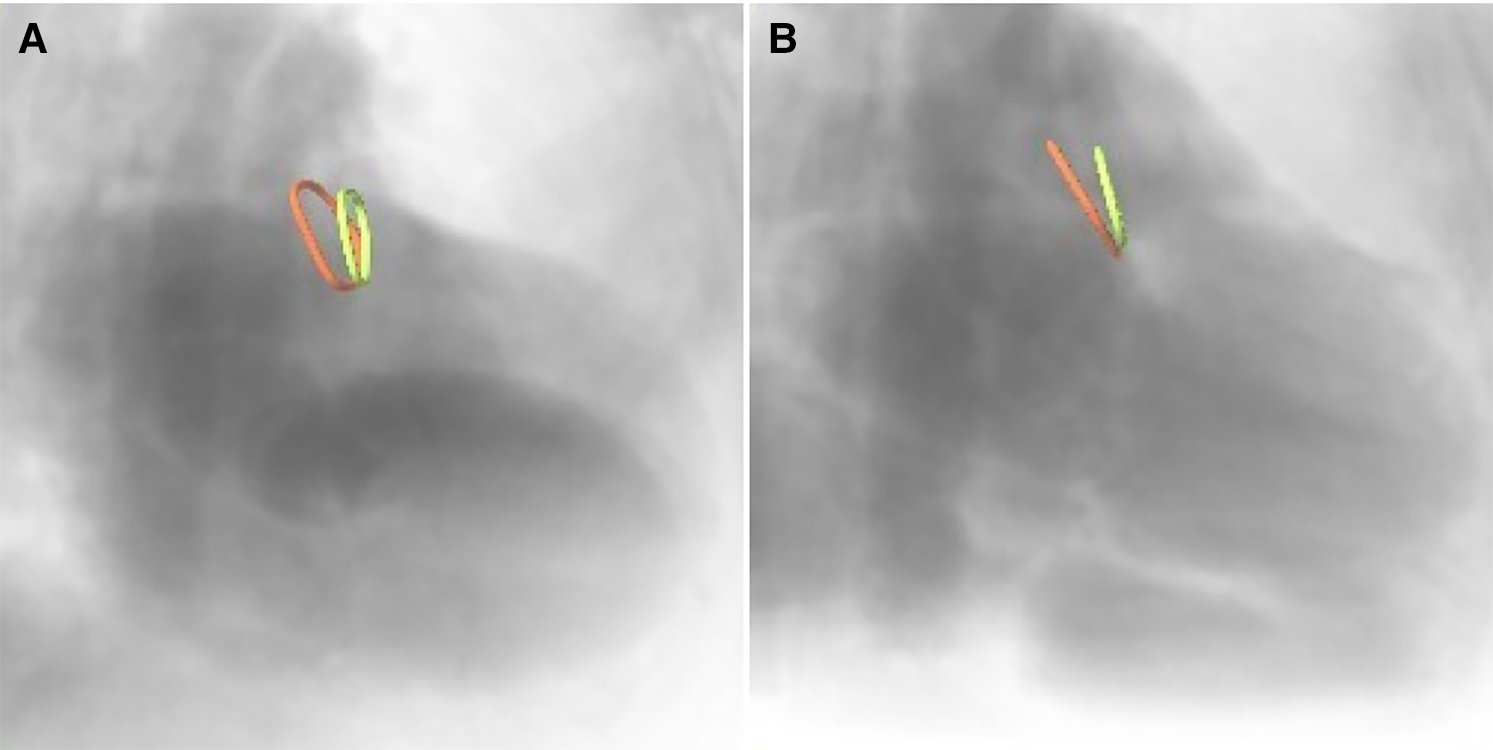

2.3.2. Angulation prediction

Furthermore, the optimal XR angulations were predicted from the CMR identified landing zones yielding orthogonal projection of the maximal diameter (Figure 3) independently by two readers. Angulations deviating by more than the 95% confidence interval were considered different to identify optimal angulations outside of the recommended angulation range (RAO20-30/CAUD20-30).

Figure 3

CMR-derived ostium (red) and landing zone (green) superimposed onto angiographical simulation in (A) the recommended angulation and (B) patient-specific optimal angulation.